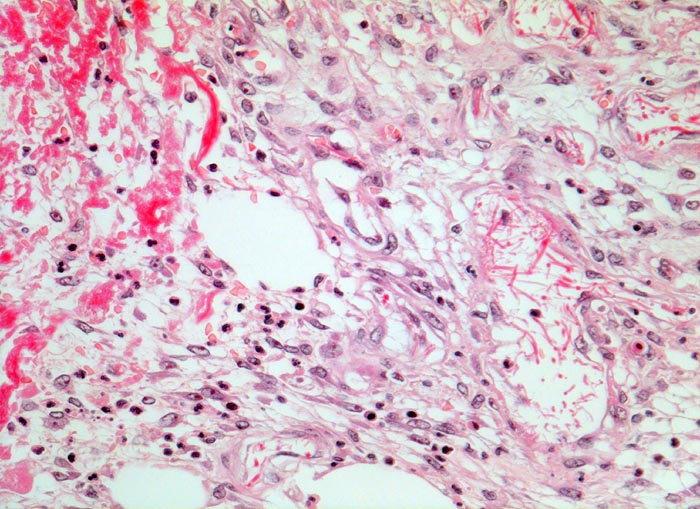

• Zweite Phase: Aufbau von Granulationsgewebe (= zell- und gefäßreiches Bindegewebe). Die Kapillarisierung (Neovaskularisation) durch Einsprossen von Blutgefäßen (Gefäßbäumchen sind als hellrote, glänzende Körnchen im Wundgrund sichtbar) sorgt für ausreichende Ernährung des Gewebes. Die Kollagensynthese durch eingewanderte Fibroblasten benötigt Vitamin C und Sauerstoff.

• Daran angrenzender Wundspalt im Bereich des subkutanen Fettgewebes mit Fibrinauflagerungen und ödematösem zellarmem Granulationsgewebe.

• An der Basis des Präparates Auseinanderklaffen des Wundspalts wegen grösserem Blutkoagel (verursacht Wundheilungsstörung).